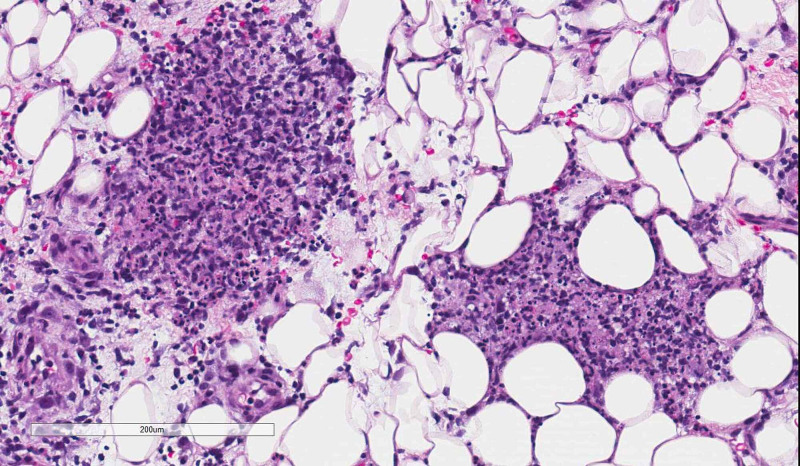

A week after his symptoms began, he presented to the emergency department and was admitted. Results pertinent to the case included a negative rapid Streptococcus A test, throat culture, and synovial fluid culture. The patient’s ESR was 41 mm/h and CRP was 190.00 mg/L. A skin biopsy of a representative subcutaneous nodule was performed that demonstrated superficial and deep dermal lymphohistiocytic inflammation, extending into the subcutis (Figures 2, 3). There were poorly formed granulomas with central coagulative necrosis and peripheral acute inflammation with conspicuous leukocytoclasis (Figure 4). Special stains for infectious organisms (Periodic acid-Schiff, Grocott’s methenamine silver, Ziehl-Neelsen, acid-fast bacilli, and tissue gram stain) were negative. Due to a lack of supportive clinical history, these microscopic findings were considered non-specific.

Figure 3. Subcutaneous mixed acute and chronic inflammation (hematoxylin & eosin, 10× magnification).

Figure 4. Poorly formed peri-eccrine granuloma with peripheral leukocytoclasis (hematoxylin & eosin, 10× magnification).